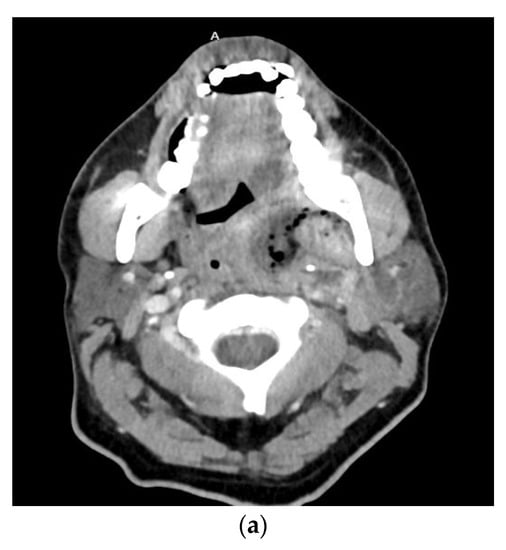

Odontogenic infections present along a spectrum of severity. A useful measure both clinically and academically is the odontogenic infection severity score developed by Flynn et al. []. This scoring system provides valuable insight into the extent of the infection based on the risk to the airway. Infections involving low risk spaces (vestibular, subperiosteal, infraorbital, buccal space) are assigned a score of one. Infections involving medium risk spaces (submandibular, submental, sublingual, pterygomandibular, submasseteric, superficial temporal, deep temporal) are assigned a score of two. Infections of high-risk spaces (lateral pharyngeal, retropharyngeal, pretracheal, danger space, mediastinum, intracranial space) are assigned a score of three. The odontogenic infection severity score is the sum of each score assigned to each fascial space involved at presentation. As an example, Figure 1 presents a patient with an odontogenic infection severity score of 6, given the involvement of the right submandibular, sublingual, and submental spaces. Previous studies have shown that when patients present with odontogenic infection severity scores of greater than or equal to five, there are increased associated hospital costs and consumption of postoperative as-needed opioid medications [,].

Figure 1.

Axial (a) and sagittal (b) computed tomography scan views of patient with right submandibular, sublingual, and submental abscess with associated odontogenic severity score of six.